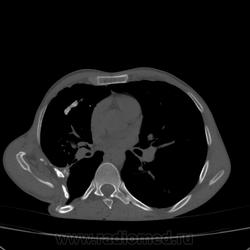

Состояние после торакопластики.

Молодой человек 30 лет, в 04 году выявлен фиброзно-кавернозный ТБ, в течение 12 месяцев лечился в стационаре, прооперирован-5реберная торакопластика справа, через 3 года переведен в 3ГДУ, в 10году снят с ДУ по излечению. Пришел провериться по ухудшению состояния. На КТ легких данных за рецидив ТБ, вроде нет. С " торакопластикой" был единственным пациентом на учете.

Состояние после правосторонней 5-реберной торакопластики по поводу ФКТ.Грубые остаточные изменения:поликистоз,буллезно-дистрофические изменения,плевропневмоцирроз правого легкого..Нет ли  мелкоочаговой диссеминации в обоих легких?Нужен Rархив.(ПТД).

Нет, это кальцинаты и более плотные уже. Архив только пленочный, 8 лет назад "цифры" не было. Можно и пленку перефотать...

Редко встречалось, а на КТ вижу впервые, спасибо за случай! На показанных изображениях отсевов не увидела.